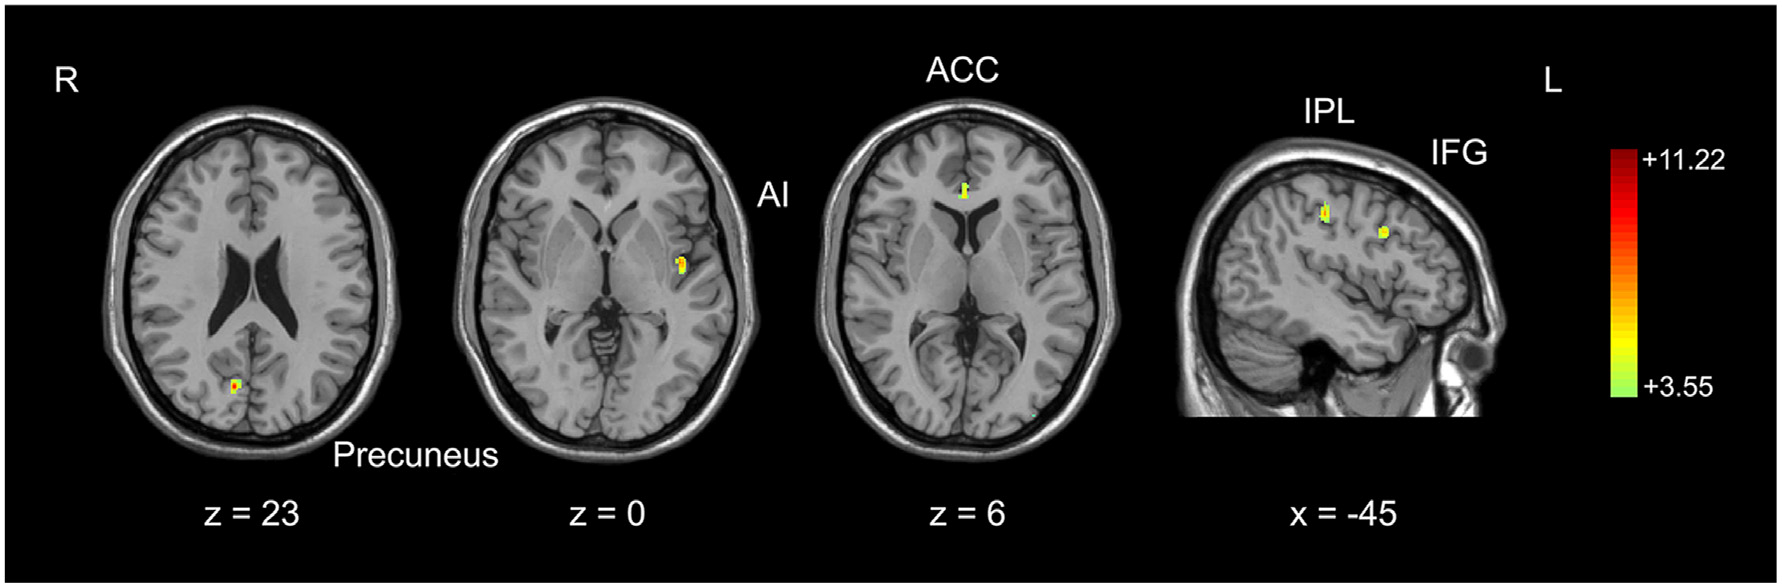

Pre-processed gray matter images in basketball players and novices were compared with a two-sample t-test (second-level) run at the whole brain level. The height of subject was set as a covariate to exclude the potential contamination caused by different sizes of brain in two groups. The t-map was set at a corrected significance level of p < 0.05. AlphaSim correction (REST_V1.8) with Monte Carlo simulation was used to correct for multiple comparisons (Poline et al., 1997; Song et al., 2011) with consideration both for the individual voxel probability and cluster size threshold. Based on the results of optimized VBM analysis, brain areas with larger gray matter volume in basketball players were identified (Figure 1). We also tested the correlation between gray matter volumes in these areas and training time in basketball players with the Pearson correlation coefficient. These areas were further selected as the seeds for the subsequent functional connectivity analyses. The seed was defined as a 6 mm radius sphere.

Figure 1

Comparison of gray matter volume between basketball players and novices. Cortical areas with more gray matter volume in basketball players compared to novices was shown. Color scale represents the significant t-values (corrected p < 0.05). L = left; R = right. Abbreviations for brain areas: ACC, anterior cingulate cortex; AI, anterior insula; IFG, inferior frontal gyrus; IPL, inferior parietal lobule.

We used an optimized VBM technique to analyze T1-weighted anatomical scanning and set height as a covariate to correct for the potential effect of contamination caused by different brain sizes in two subject groups. It was found that basketball players had larger gray matter volumes than novices in multiple brain areas. These areas included right precuneus, left anterior insula (AI), right anterior cingulate cortex (ACC), left inferior frontal gyrus (IFG) and left inferior parietal lobule (IPL; Figure 1; Table 1). These areas were selected as the seeds for the functional connectivity analyses. The inverse contrast analysis did not show larger volumes in novices compared to players in any brain areas. No significant correlation was found between the gray matter volume and training time in five seed regions in basketball players.